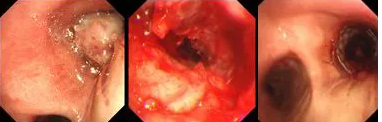

原來,秦爺爺入院時診斷為“右主支氣管”鱗狀細胞癌伴壞死。他的右主支氣管被腫瘤完全堵塞,混合性狹窄。面罩吸氧10升/分的狀況下,指脈氧只有85%,無法平躺,呼吸困難,病情十分危急,隨時有生命危險。

經(jīng)評估并與家屬溝通同意后,歐陽海峰副院長決定為患者實施TTS氣道支架手術(shù)。手術(shù)當(dāng)天,在麻醉手術(shù)中心的配合下,歐陽海峰副院長為患者在局麻下快速凍切腫瘤組織,實現(xiàn)右主支氣管再通,并經(jīng)氣管鏡活檢孔道迅速植入14*30 TTS支架一枚。支架植入過程耗時僅6秒,迅速緩解了患者的氣短瀕死癥狀。